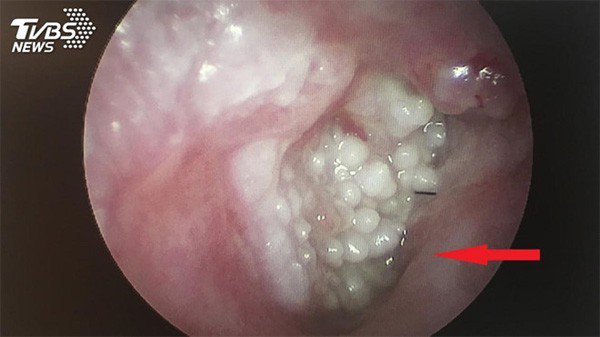

Mới đây, một người đàn ông 70 tuổi ở Đài Loan, Trung Quốc đã được các bác sĩ phát hiện có chi chít sùi mào gà mọc trong lỗ tai gây ngứa ngáy, khó chịu và ảnh hưởng đến thính lực.

Khai thác tiểu sử được biết, người này hay đi cắt tóc, gội đầu tại một tiệm quen và họ có dịch vụ lấy ráy tai nên lần nào đến đây ông cũng yêu cầu.

Ông cho biết, dụng cụ thực hiện lấy ráy tại tiệm này là một cây ngoáy tai bằng kim loại. Theo các bác sĩ, có thể, dụng cụ này chính là nguồn lây sùi mào gà nếu chúng không được vệ sinh hoặc diệt khuẩn trước khi sử dụng.